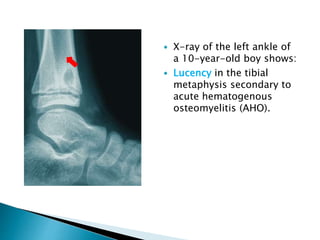

 X-ray of the left ankle of

a 10-year-old boy shows:

 Lucency in the tibial

metaphysis secondary to

acute hematogenous

osteomyelitis (AHO).